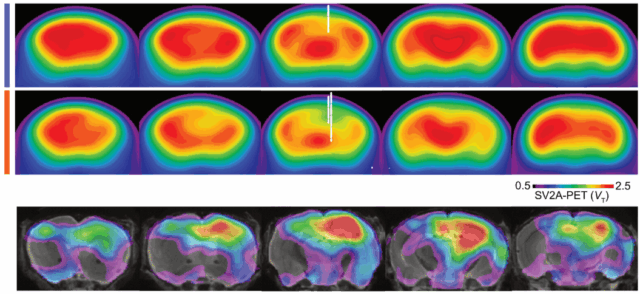

SV2A-PET imaging uncovers cortical synapse loss in multiple sclerosis

Background In Multiple Sclerosis (MS), focal lesions and white matter pathology have been long studied. Grey matter changes however, particularly in the cortex, are increasingly recognised